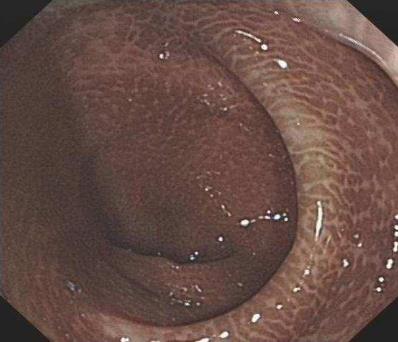

“武汉汉西博仕肛肠医院”专家说,有些便秘患者有长期的清茶,这会引起依赖性。清茶虽然能使人顺利清肠一段时间,但也会产生不良的后果,甚至导致结肠变黑。通常理解,结肠是黑色的,大肠的粘膜变黑,这是粘膜色素沉着病的表现。黑变病还能引起大肠其他疾病,不容忽视。